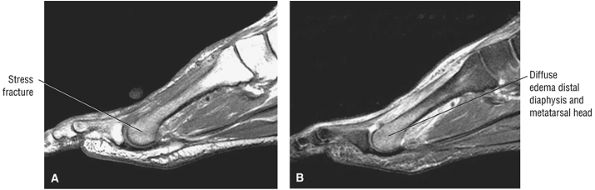

Localized edema

-

Peroneal retinacular thickening

Tenosynovitis

Tendon subluxation